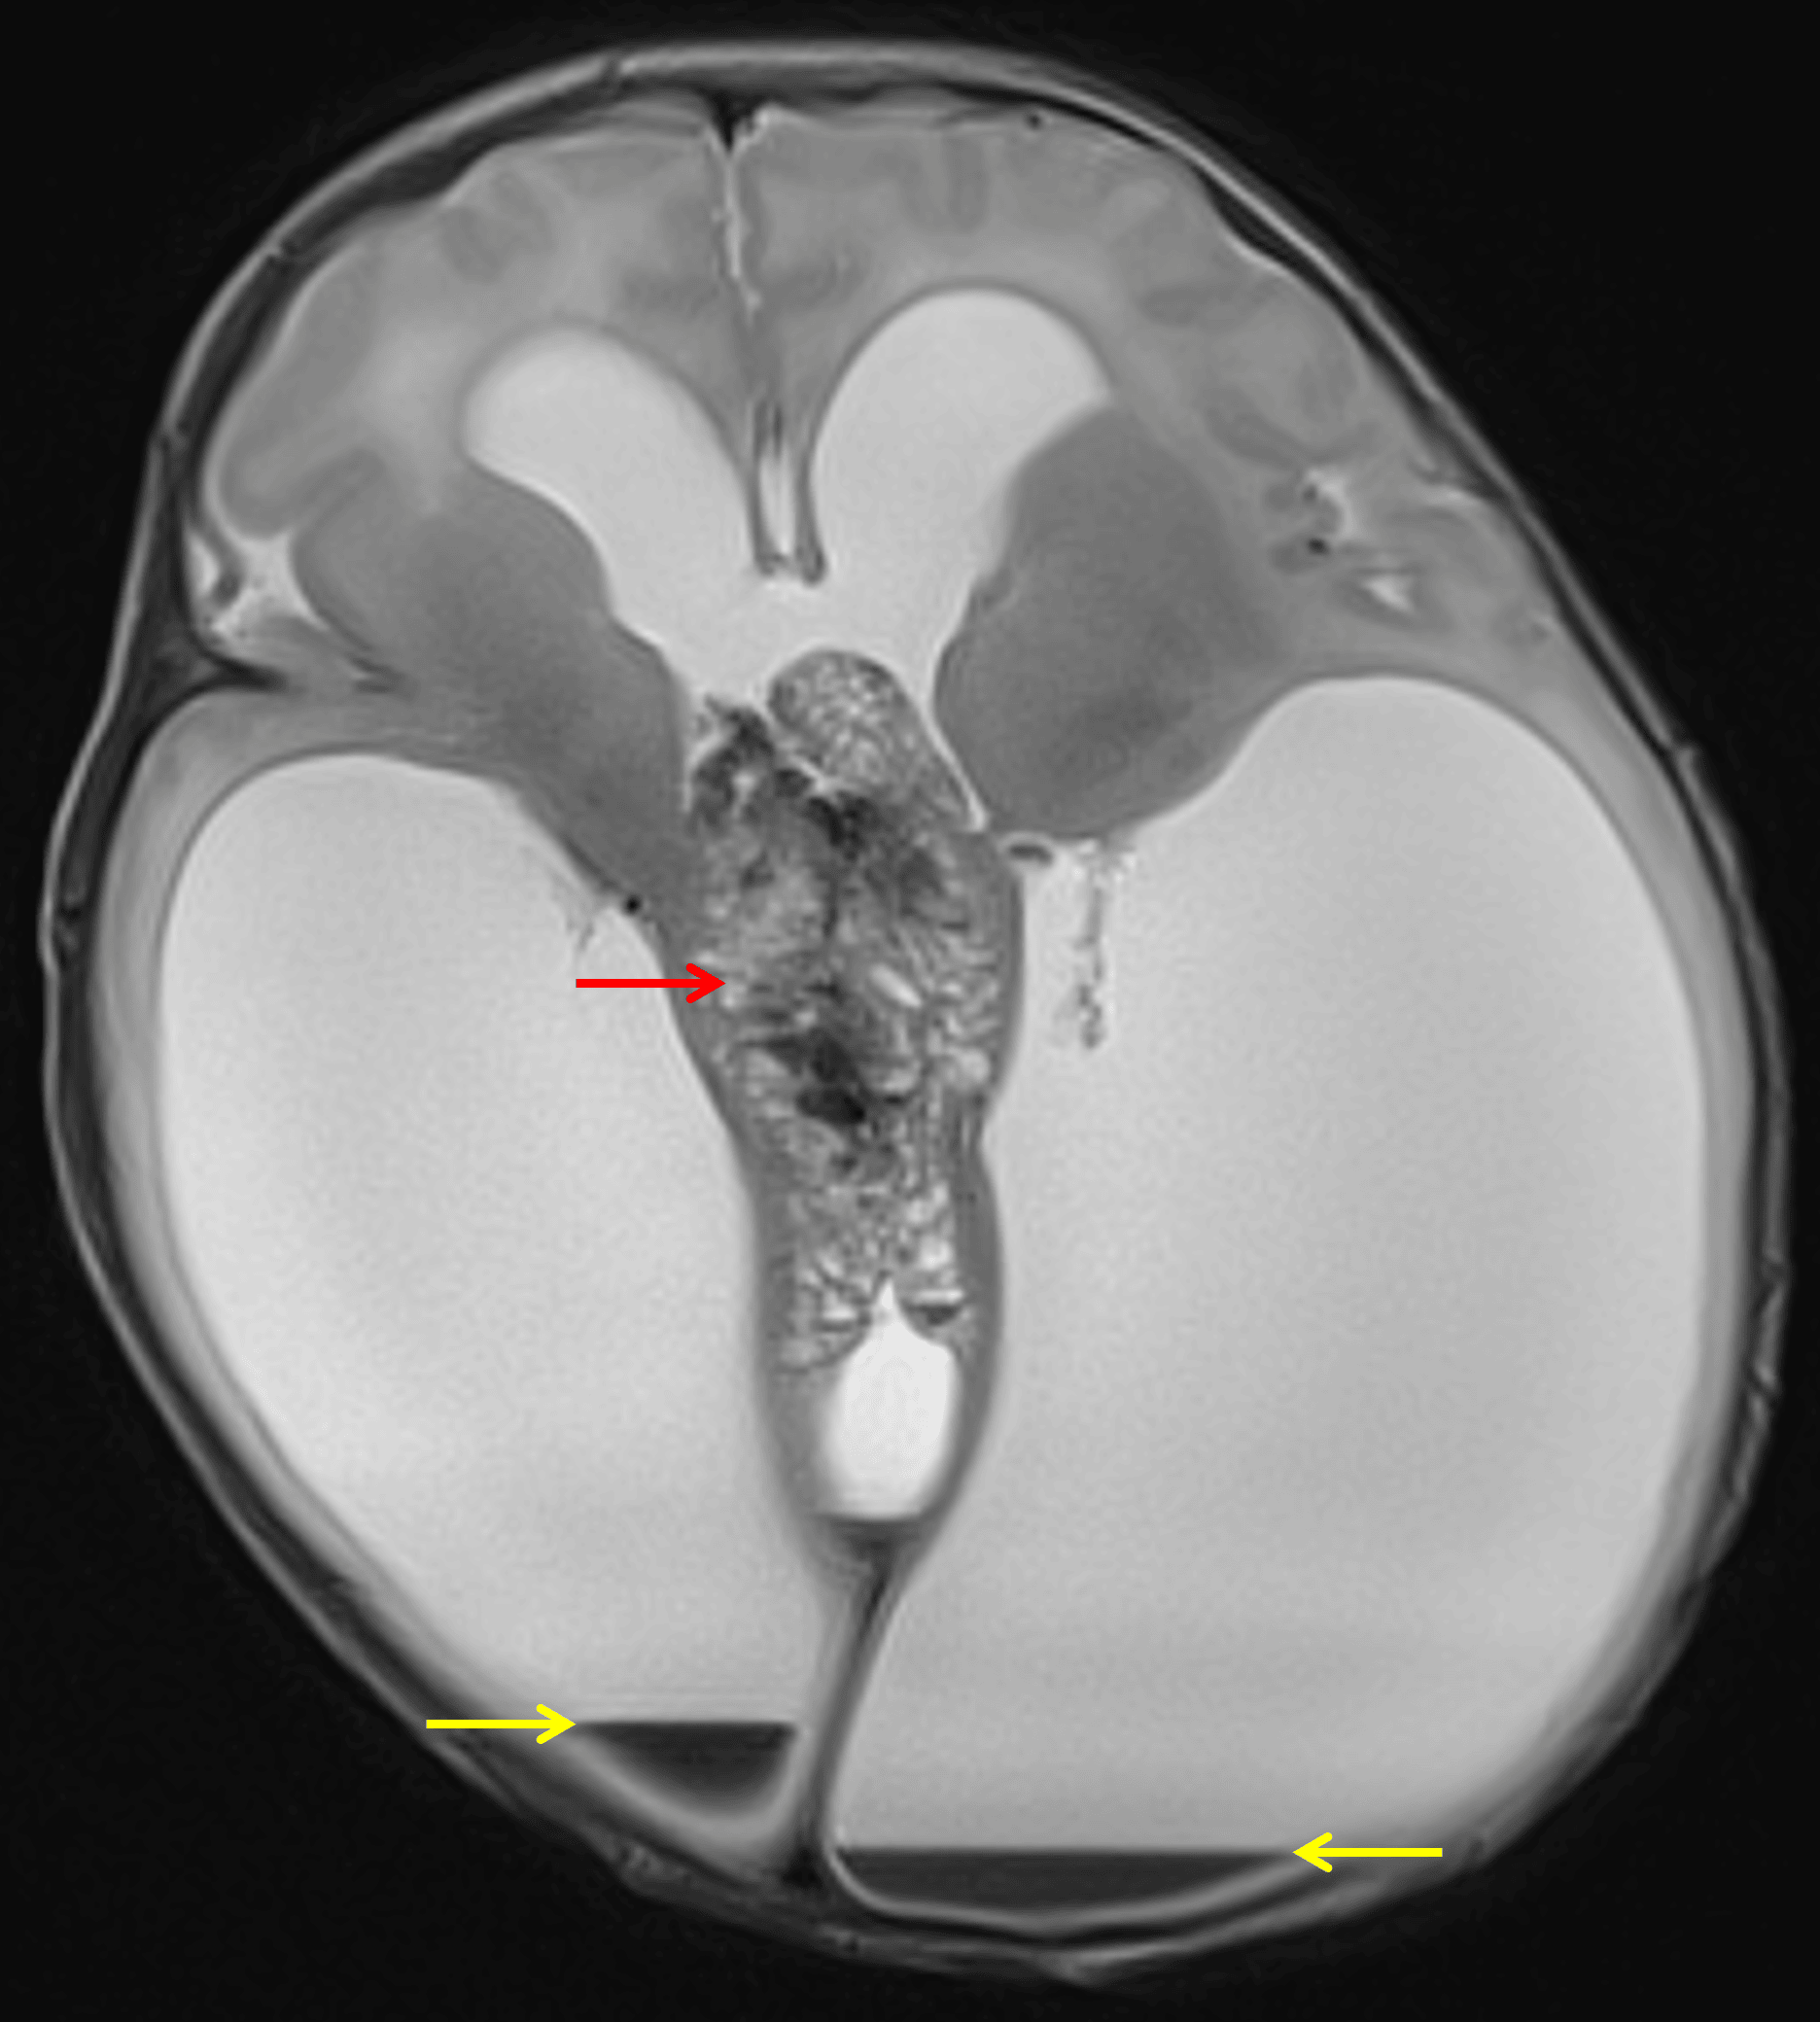

Heterogeneous midline mass (red arrow) with associated severe obstructive hydrocephalus and small volume intraventricular hemorrhage (yellow arrows).